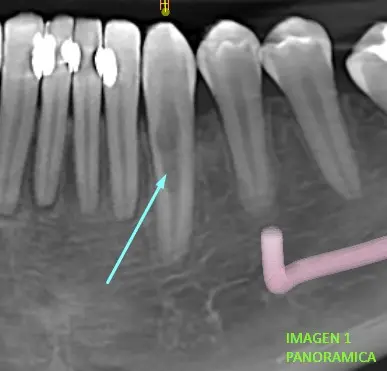

Luego realizada la tomografía se puede

visualizar en la imagen de vista panorámica (imagen 1.), una forma irregular

del canal radicular de pieza dentaria 33 a comparación de piezas dentarias

aledañas.